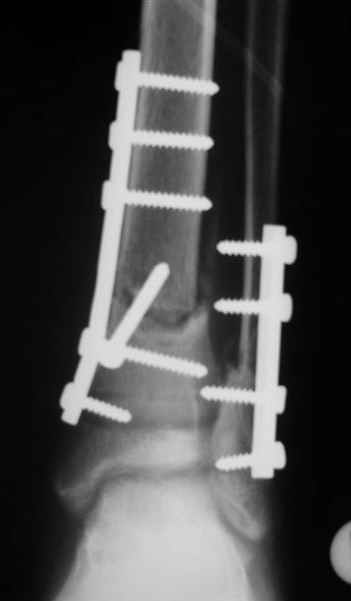

АВФ -отдельная история в нашем краю, поэтому последний вариант -открытая репозиция, что я и сделал: Без мобилизации отломков б.б. репозиция м.б. не получалась. Первым делом фиксировал перелом м.б. кости пластиной на 4 4,5 мм винтах,

при ревизии зоны перелома б.б. кости сохранялось смещение дистального отломка кпереди, пришлось принять меры и решить эту проблему.

На прямой проекции видно угловое смещение отломков малоберцовой кости, обуславливающий и

наклон тарана, да и вальгус отломков б.б. , а на боковой проекции -смещение отломков

кпереди и по длине.

Коррекция углового смещения и смещения по длине отломков м.б. кости автоматом устраняет

наклон тарана , что необходимо для нормальной функции голеностопа. Так оно и произошло во

время операции.

Единственный момент, о котором я и уже писал - не наступило спонтанной анатомичной

репозиции отломков б.б., поэтому после репозиции пришлось использовать тягловый винт и

*укрепить* достигнутое положение узкой пластиной динамической компрессии.

Послеоперационные снимки сегодня посмотрел - все выглядит вполне анатомично, кроме длины

винтов на м.б. кость - слегка переборщил:-(( Не было камеры с собой , но как только

пересниму картинки обязательно вышлю.

Поэтому фиксация м.б. кости все-таки показана....